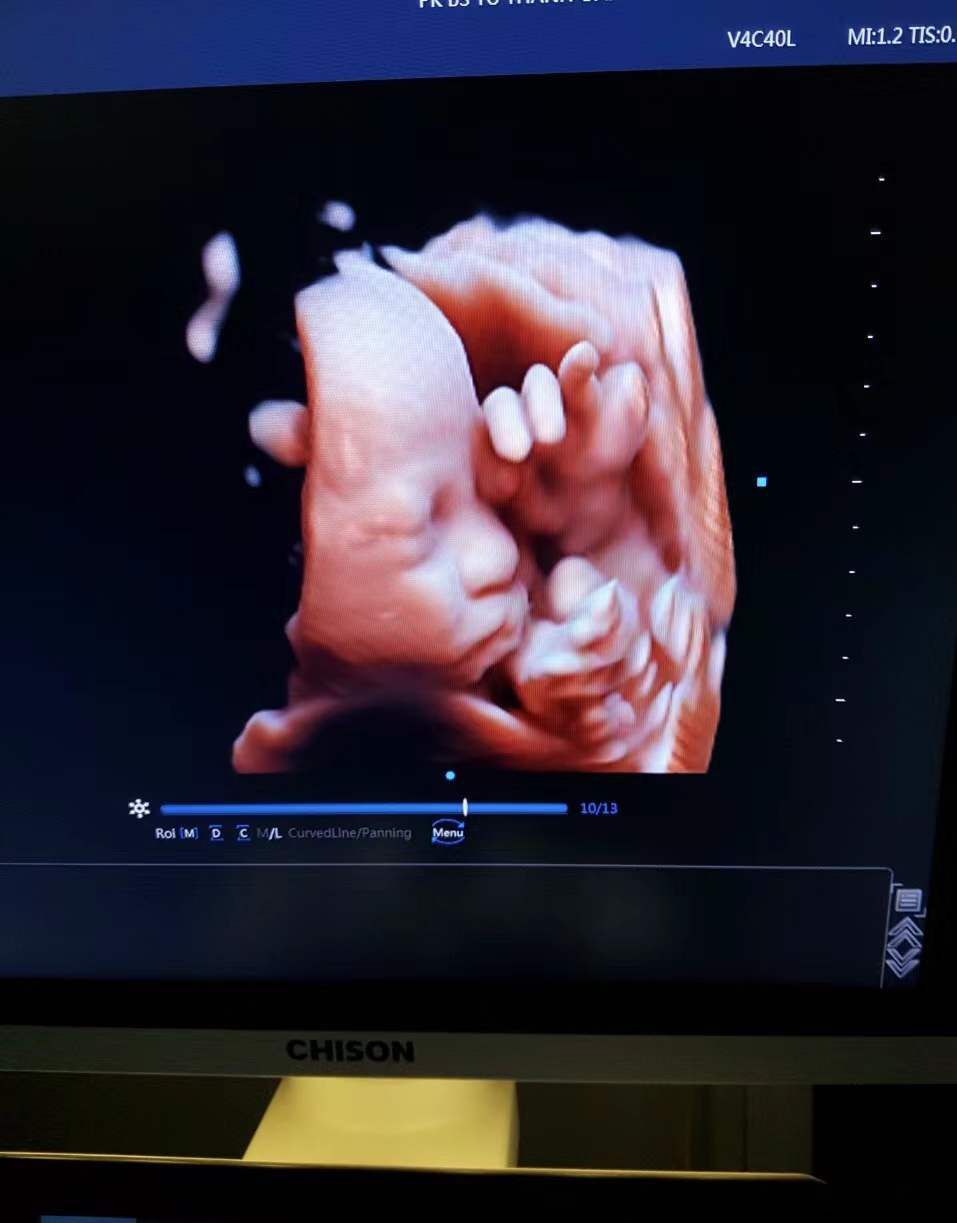

There are several different types of obstetric ultrasound machines, including 2D, 3D, and 4D ultrasound machines. 2D machines produce two-dimensional images, while 3D machines create three-dimensional images. 4D machines produce real-time 3D images that show the movement of the fetus.

Real-time monitoring: 4D ultrasound machines provide real-time monitoring of the fetus, allowing doctors to observe fetal movement and behavior.